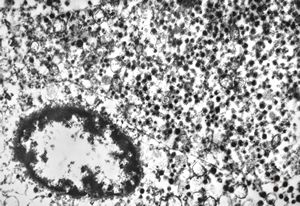

F, 68y. | APUD carcinoma mammae - Bodian impregnation